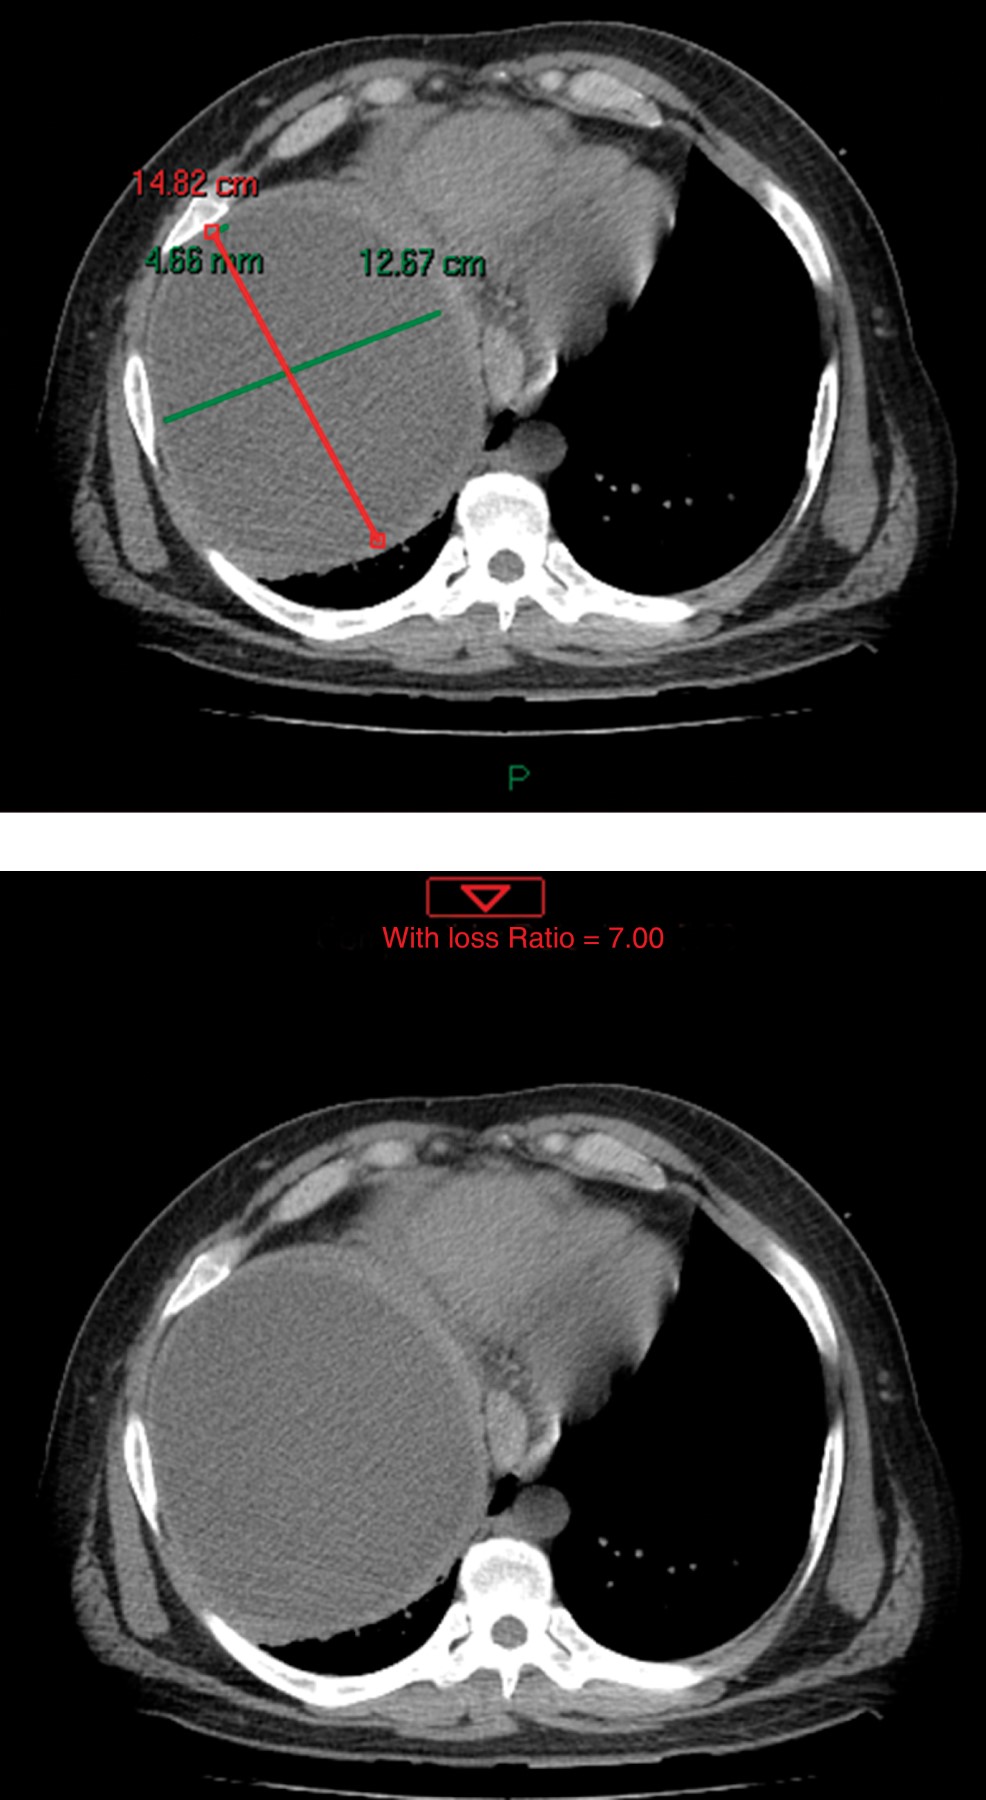

A su ingreso se mostraba ansioso, alerta, orientado; valoración inicial ATLS (Advanced Trauma Life Support), sin compromiso hemodinámico, neurológicamente sin déficit, tórax con dermoabrasiones, campos ventilados de manera bilateral, hipoventilación basal de hemitórax derecho, abdomen con marcas cutáneas de neumáticos, blando, depresible con dolor a la palpación generalizada profunda, datos de irritación peritoneal en cuadrantes inferiores, extremidades con dermoabrasiones en antebrazos. Se realizan placas de protocolo de ATLS, se observó en la radiografía de tórax (Figura 1) hemitórax derecho con elevación del hemidiafragma, sin neumotórax o derrame pleural, se efectúa FAST (Focused Abdominal Sonography for Trauma) primario sin revelar líquido en pericardio, espacio hepatorrenal, esplenorrenal o en pelvis, se realiza tomografía axial computarizada simple y contrastada toraco-abdomino-pélvica (Figuras 2 y 3) en la que se observa imagen compatible con quiste hepático simple de 12.6 x 14.7 cm.

Figura 3